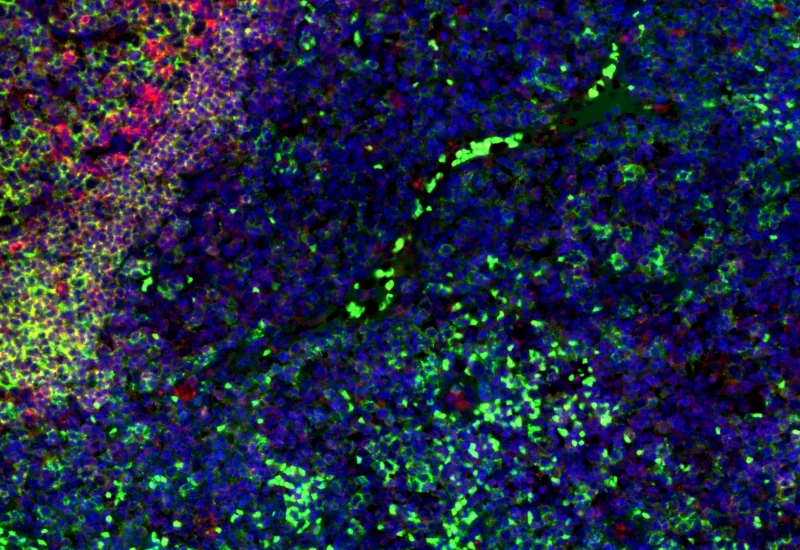

Original Image

Nuclei detection